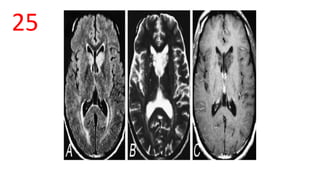

CRYPTOCOCCOSIS – Soap bubble pattern

• A – T2 Flair-caudate hyperintensity

• B – T2– Soap bubble caudate

• C – T1C+ - no enhancement